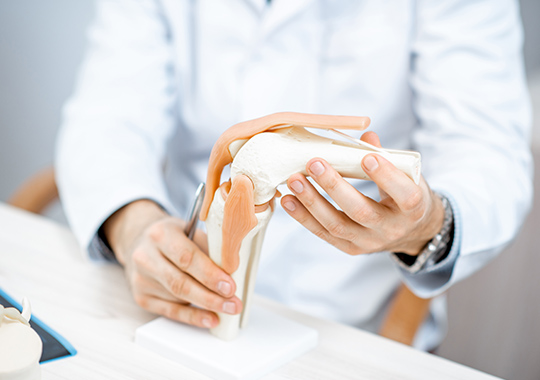

Orthopedic Surgery

膝や股関節は加齢や外傷、日常生活での負担によって痛みや変形を生じやすい部位です。当外来では、専門医が診断を行い、保存療法や手術など複数の選択肢から症状に応じた治療を検討します。人工関節置換術や骨切り術などにも対応し、患者様の生活機能の改善を目指した診療を行っています。